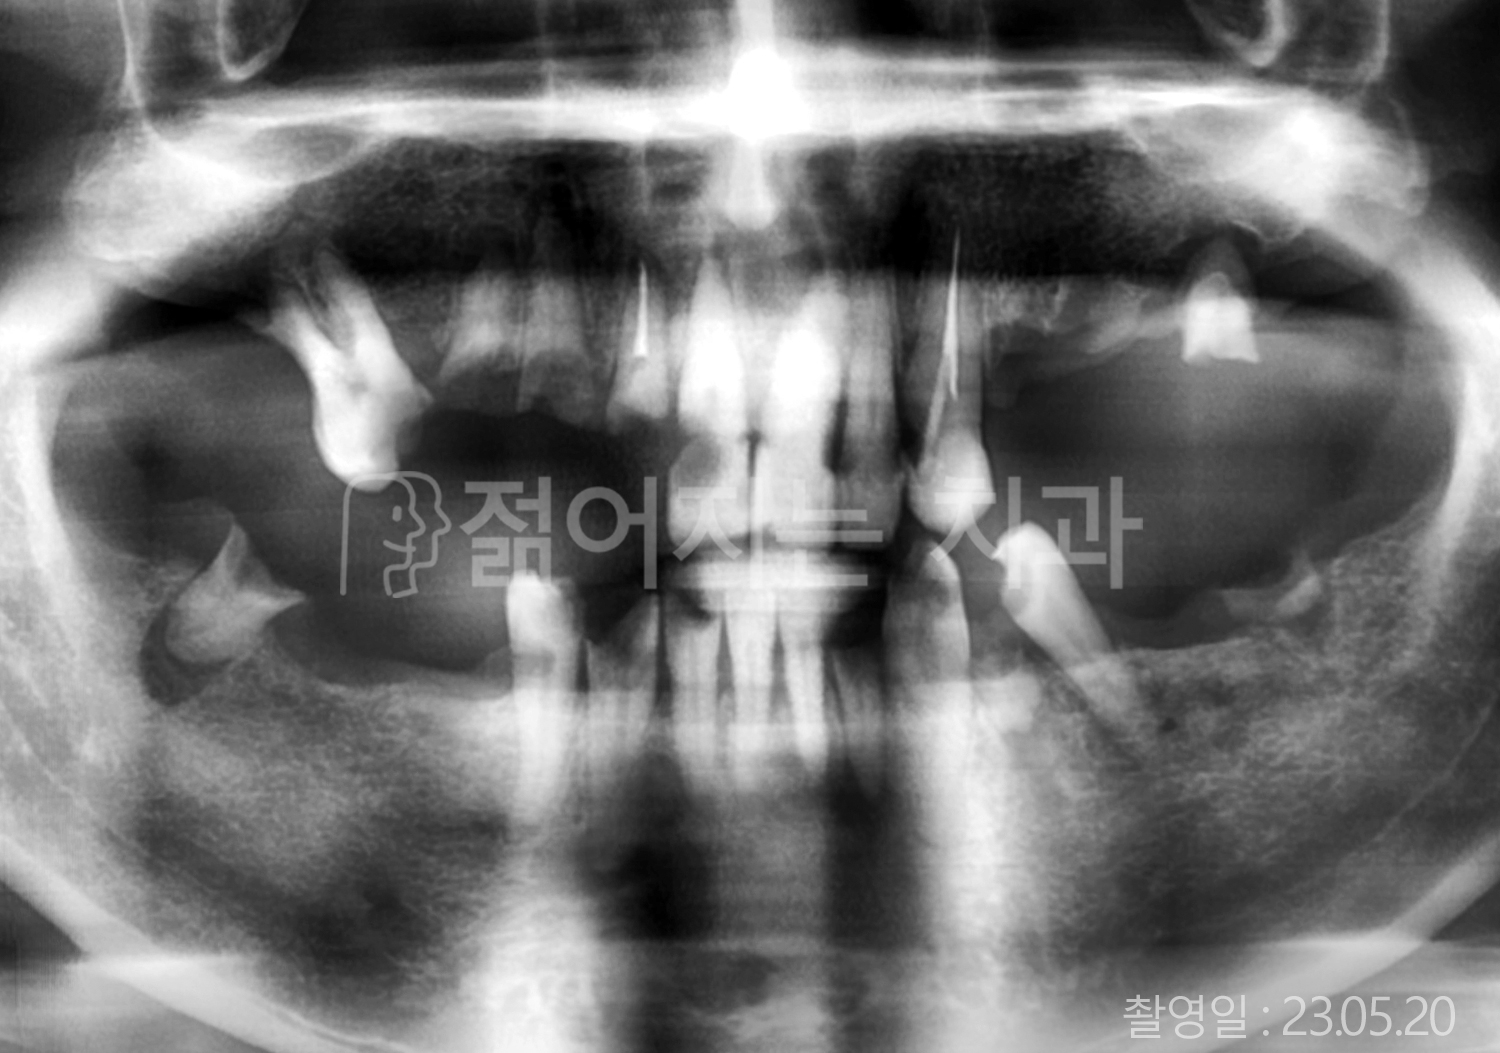

치료사례(치아)

• 70대 고혈압, 고지혈증 전체치아 10개 이상 임플란트

• 60대 당뇨, 간염 전체치아 10개 이상 임플란트

• 80대 골다골증 전체치아 6개 이상 임플란트

• 70대 고혈압, 당뇨 전체치아 10개 이상 임플란트

• 60대 간 질환 전체치아 10개 이상 임플란트

• 60대 전체치아 10개 이상 임플란트

• 70대 전체치아 10개 이상 임플란트

• 50대 전체치아 10개 이상 임플란트

• 60대 고혈압, 고지혈증 전체치아 10개 이상 임플란트

• 40대 고지혈증, 뇌혈관 질환 전체치아 10개 이상 임플란트